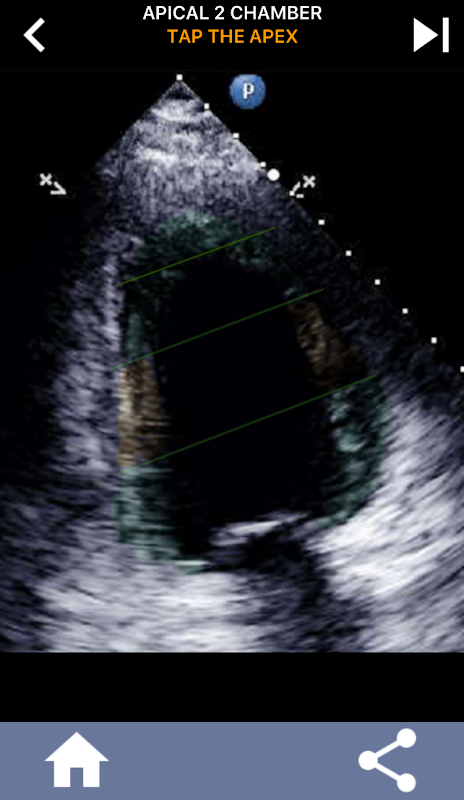

Это приложение содержит все эхо-изображения, показывающие сегментированный миокард АНА, и предложит вам нажать на нужный сегмент. Я лично считаю, что повторяющиеся тесты лучше всего подходят для меня, когда мне нужно быстро выучить / запомнить предмет. Если вы студент УЗИ, изучающий эхо / TTE, я думаю, это будет отличным дополнением к вашей учебе.